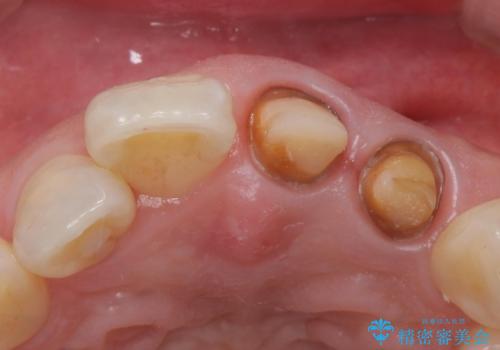

- 前歯の変色を主訴に来院された患者様です。

再根管治療からのやり直しも提案しましたが、特にご希望されなかったためクラウンでの修復処置のみ行います。

歯は根管治療が終了して時間が経つとだんだん茶色く変色していきます。